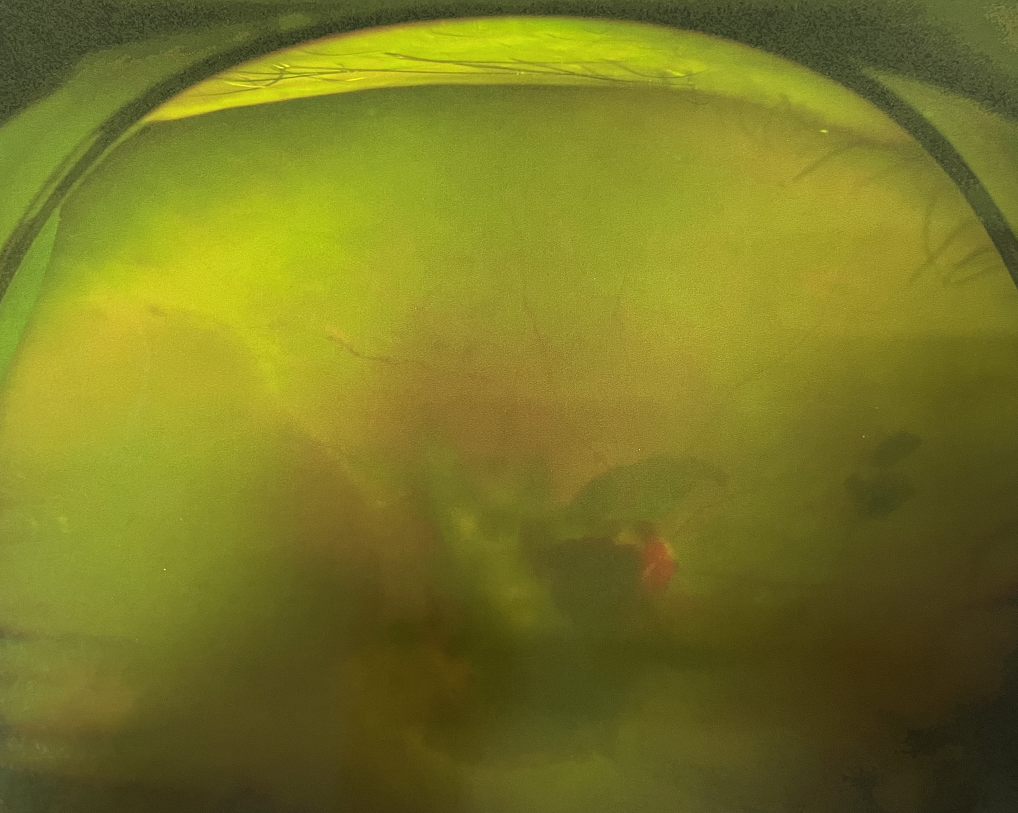

右眼術(shù)前

四十多歲的王女士,患高血壓病及Ⅱ型糖尿病多年,一直靠藥物控制血壓和血糖。去年,王女士右眼看手機(jī)時感覺視物不清,總感覺眼前有一層霧,視力也逐漸下降,于是來廈門大學(xué)附屬廈門眼科中心就診。

眼底病??茝埿』⑨t(yī)生檢查后,診斷王女士為“雙眼玻璃體積血、雙眼糖尿病視網(wǎng)膜病變V期”。(V期即5期,纖維增生期,出現(xiàn)纖維膜,可伴視網(wǎng)膜前出血或玻璃體出血。)

張小虎醫(yī)生為王女士進(jìn)行右眼玻璃體腔注藥術(shù),3天后進(jìn)行右眼23G玻璃體切割術(shù)后視力有所提升。

4個月后王女士來院取硅油,取油后視力恢復(fù)到0.6。“當(dāng)時來的時候真的只能看到模糊的影子,特別害怕覺得完了,想說眼睛估計(jì)要瞎了,沒想到手術(shù)后視力竟然提升了,現(xiàn)在也看得比較清楚了。”王女士說到。

張小虎醫(yī)生表示,糖網(wǎng)病進(jìn)展到嚴(yán)重增殖期帶來的視力損傷往往是極其嚴(yán)重的,目前王女士右眼從術(shù)前0.02恢復(fù)到術(shù)后0.6,已屬十分難得。